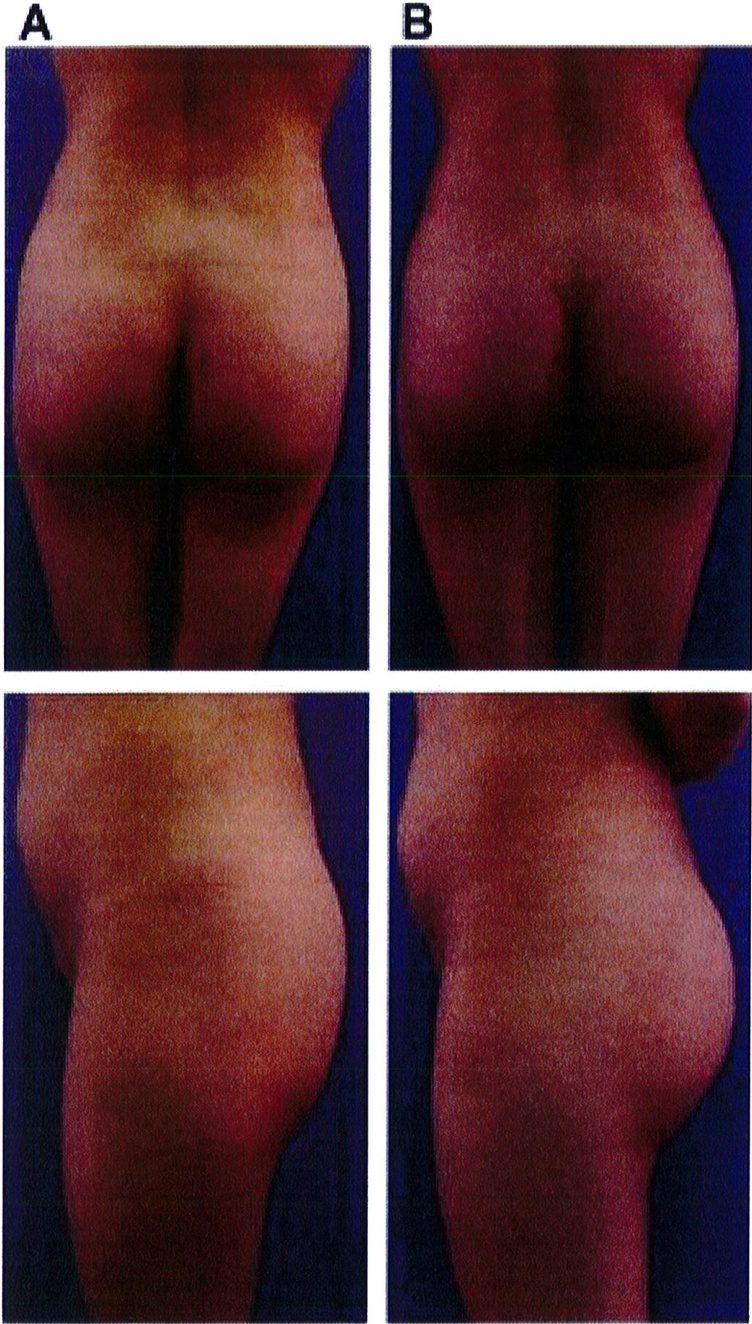

Hình. 18.. (A) Hình anh trước và (B) và sau phẫu thuật làm đầy mông của bệnh nhân được đặt khối implant dưới cân thể tích 225 mL, hai bên.

Hình. 18. (tiếp)

Bệnh nhân 31 tuổi tiền sử khỏe mạnh, có chỉ định nâng mông bằng implant do thiếu hụt thể tích. Hai khối anatomic implant 225 mL polyurethane dạng gel được đặt ở vị trí dưới cân. Sau phẫu thuật không ghi nhận biến chứng trong suốt quá trình hồi phục, vết mổ liền tốt (Hình 18).